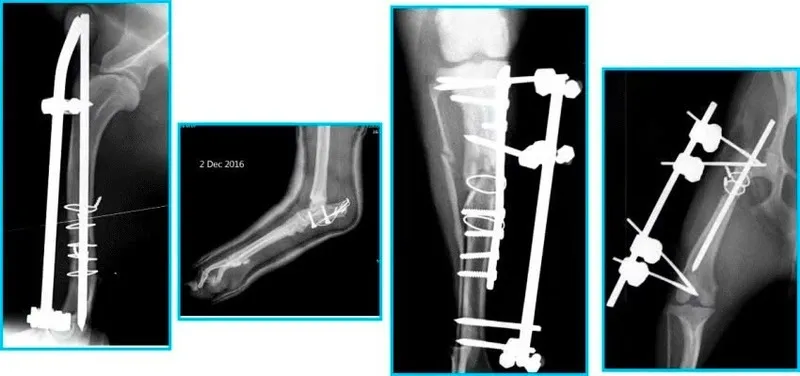

Phẫu thuật điều trị mèo bị trật khớp chân sau tại bệnh viện thú y*Hình 1: Can thiệp ngoại khoa là giải pháp tối ưu cho các ca trật khớp nặng ở mèo.*

- Chụp X-quang kỹ thuật số: Xác định chính xác vị trí trật khớp và kiểm tra xem có mảnh xương vỡ nào hay không.

Kiểm tra lâm sàng cho mèo trước khi can thiệp y tế*Hình 3: Chẩn đoán hình ảnh giúp xác định mức độ nghiêm trọng khi mèo bị trật khớp chân sau.*

Tùy vào tình trạng mèo bị trật khớp chân sau, bác sĩ sẽ chọn kỹ thuật:

- Tạo hình rãnh xương bánh chè: Khoét sâu thêm rãnh xương để xương bánh chè không còn bị trượt ra ngoài.

- Cắt chỏm xương đùi (FHO): Áp dụng cho trật khớp háng nặng hoặc thoái hóa. Cơ thể mèo sẽ tự tạo một “khớp giả” bằng mô xơ, giúp mèo đi lại mà không còn đau đớn.

| Ngày 1 | Mèo ta 4.5kg, chân sau phải biến dạng, đau cấp tính. | Chụp X-quang, xác định gãy sụn khớp. Phẫu thuật đóng đinh. | Cố định được vị trí xương, mèo tỉnh táo sau gây mê. |

| Tuần 6 | Ảnh chụp X-quang cho thấy xương liền hoàn hảo. | Tháo nẹp (nếu có), bắt đầu cho vận động tự do trong nhà. | Mèo bị trật khớp chân sau hoàn toàn phục hồi chức năng. |